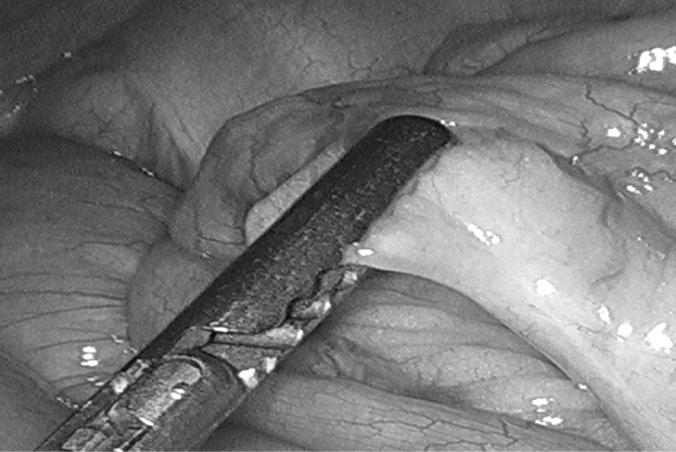

Both patients underwent laparoscopic surgery with successful resection of the lesions. The details and crucial points of the laparoscopic approach to these tumors are described with specific attention to its appropriateness and safety in treating GIST tumors. Attention to particular details of the manipulation and management of the bowel in the face of obstruction and removal of the lesions is described.